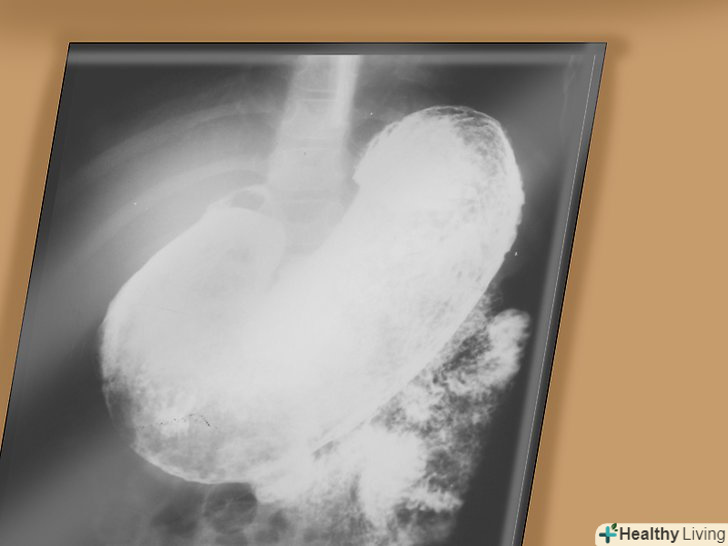

- Рентгеноскопія. Для даної процедури вам буде потрібно випити білу рідину з вмістом барію. Барій обволікає стравохід, шлунок і кишечник, що робить ваші органи помітніше на рентгені. Рентген дозволяє лікарю виявити проблемні місця вашої травної системи.